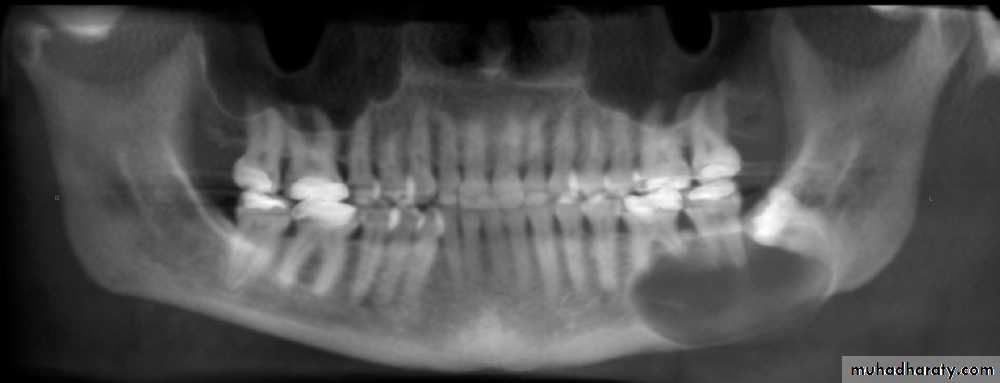

Radiographic Features:

Most lesions are discovered on routine radiographic examination.A well-defined radiolucency of bone apical to the offending tooth. Loss of the apical lamina dura.

The lesion may be circumscribed or ill defined.

The size is variable.

Cyst of long standing may undergo an acute exacerbation which lead to abscess formation.Radiographic Features.

in most cases is identical to periapical granuloma,but, the cyst may be of greater size than the granuloma.Occasionally the apical periodontal cyst exhibits a thin, radiopaque line around the periphery of the radiolucent area, and this indicates a reaction of the bone to the slowly expanding mass.